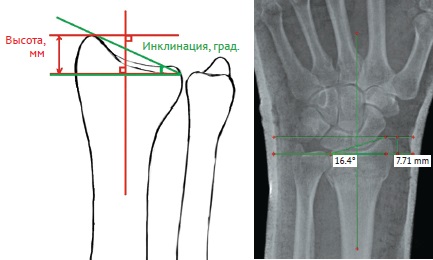

Нами были изучены и проанализированы основные рентгенологические параметры поврежденного сегмента лучевой кости как на предоперационном этапе, так и после операции (рис. 1, 2, 3).

Рис. 1. Оценка высоты и инклинации лучевой кости на предоперационном этапе: уменьшение нормальных величин обоих параметров

Fig. 1. Assessment of the radial height and radial inclination at pre-operative period: it is noted the reduction of the normal value of both parameters

Рис. 2. Оценка ладонного наклона суставной фасетки лучевой кости на предоперационном этапе: отмечается отрицательный ладонный наклон

Fig. 2. Volar tilt assessment at pre-operative period: a negative volar tilt of distal radius